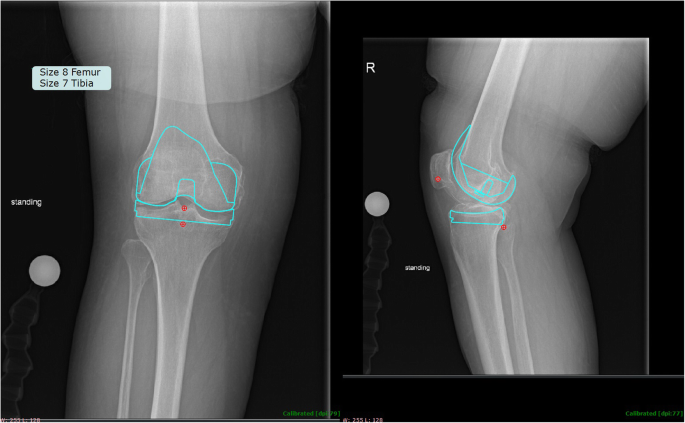

Using demographic data to predict implant sizes was both more accurate and more precise when compared to radiographic templating techniques. The multivariate linear regression model predicted within one size of the implanted femoral and tibial components 90.1 and 95.6% of the time, compared to 86.2 and 85.1% with radiographic templating, respectively. The multivariate linear regression model predicted within two sizes of the implanted femoral and tibial components in every case, compared to within four sizes for radiographic templating, respectively. Similarly, the multivariate linear regression model averaged within 0.66 and 0.61 sizes from the implanted femoral and tibial components, compared to within 0.81 and 0.81 for radiographic templating, respectively. The results demonstrate that the use of demographic data in predicting femoral and tibial implant size outperformed radiographic templating on every measure. An example where demographic data perfectly matched that implanted, while radiographic templating was off by four sizes for both the femoral and tibial components, respectively, is shown in Fig. 3. Similarly, an example calculation of how the demographic data may be used to predict component sizes is shown in Fig. 4.

Example case where demographic information outperformed radiographic templating. Here the patient’s demographic information calculated a size-4 and size-3 femoral and tibial component, respectively; perfectly matching the sizes implanted. Meanwhile, radiographic templating showed good fit with a size-8 and size-7 femoral and tibial component, respectively